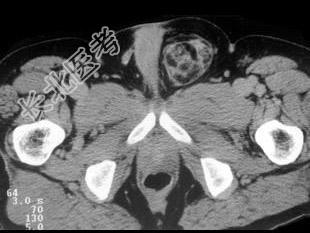

- 单项选择题男,62岁, 左腹股沟可触及肿块,结合所示图像, 正确答案是 ( )

A、斜疝

B、精索脂肪肉瘤

C、淋巴瘤

D、黑色素瘤

E、以上都不是